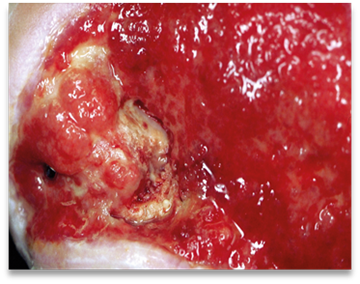

- the tissue quality. Are there signs of granulation or necrosis?

- the periwound (surrounding) skin and the wound edge